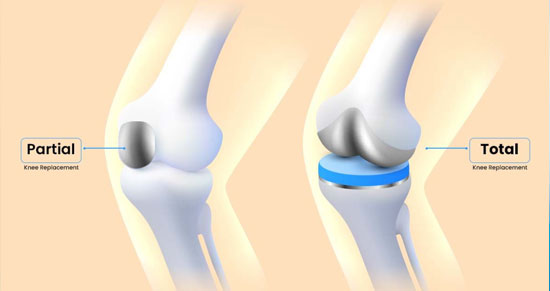

Knee Replacement

If your knee is severely damaged by arthritis or injury, it may be hard for you to perform

When debilitating pain, accompanied by stiffness, swelling and limited motion in your knee keep you away from your daily activities, it may be time to consider total knee replacement. The development of total knee replacement technology began more than 30 years ago. Each year, more than 800,000 people worldwide undergo knee replacement surgery to help ease pain and stiffness and restore mobility. The most frequent cause of discomfort and chronic knee pain is arthritis, which is one of the leading cause of disabilities in India. In fact, it’s estimated that 1 in 5 people in India has arthritis, and two-thirds are above the age of 60. Of the more than 100 types of arthritis, the following three are the most common causes of joint damage....more